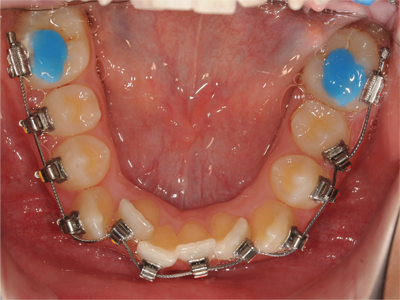

Class II Div II |